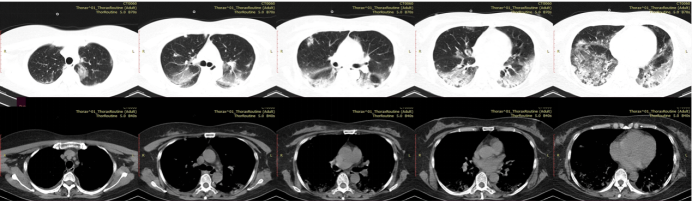

经多学科讨论最终诊断为抗合成酶抗体综合征相关间质性肺疾病。予加用甲强龙40 mg q12h静滴+免疫球蛋白20 g qd治疗5 d,患者氧合指数<150 mmHg,活动后气促明显,同时辅予清醒俯卧位(>12 h/d)改善氧合,2周后患者体温平,咳嗽、胸闷气促症状逐步好转,CRP降至正常,氧合指数明显改善,不吸氧氧饱和度可维持在95%以上(PaO2/FiO2>250 mmHg)。6月30日复查肺部CT可见双肺病灶较前吸收好转(图2)

图片

2  患者胸部CT(2022年6月30日)